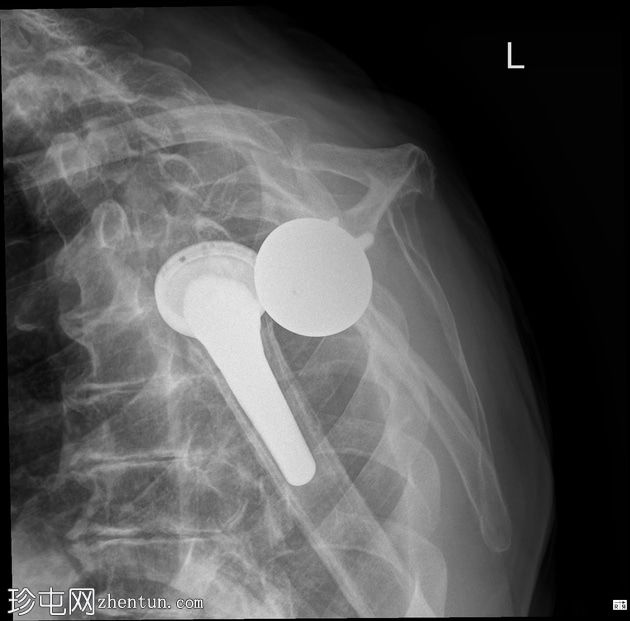

X光片

正面

反式全肩关节置换术后肱骨假体前脱位。无假体周围透亮区或骨折。